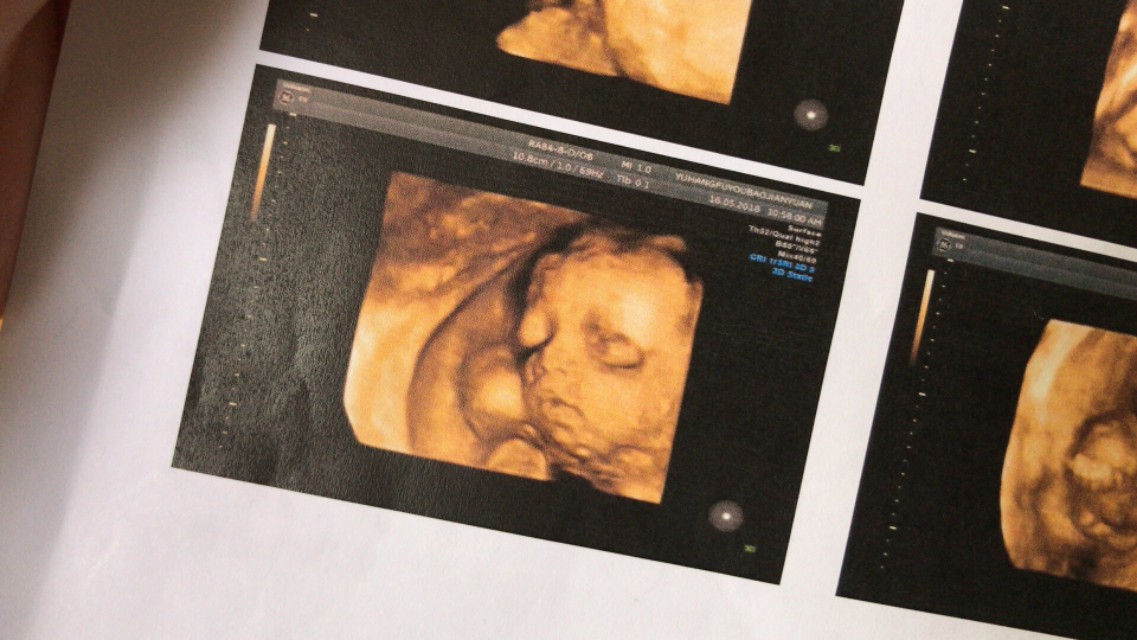

(第一次看到小家伙的照片,是个漂亮的小宝宝,眼睛真大)